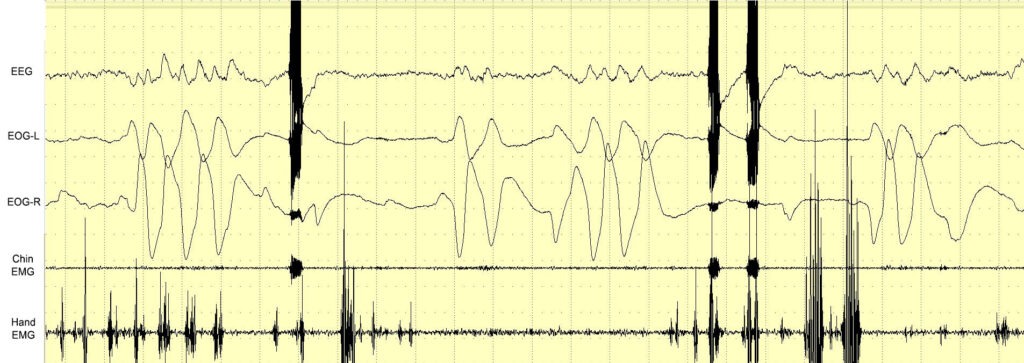

As humans spend one-third of their lives asleep, many studies have explored the possibility of controlling dreams. For the first time, we tested electrical brain stimulation (EBS) of the motor cortex during REM sleep to observe how it is incorporated into dreams. Electrodes were implanted in the motor cortex of one man with the ability to induce lucid dreams (LDs). Under polysomnographic (PSG) observation, the cortex was stimulated by an alternating current during REM sleep, sleep paralysis (SP), and lucid dreams (LDs). The results show that, within a certain current range, EBS did not wake the participant. Though he could not recall specific motor stimulations in REM sleep, some irregular changes in dream plots were observed. The most interesting results were observed during an LD in which it was possible to intentionally observe an EBS-induced contraction, which interacted with a dream object. In some cases, sensory feedback from the EBS of the motor cortex was perceived when the PSG data showed REM sleep and muscle atonia. Though some of the results need further confirmation, we discuss how the obtained data could present new horizons for controlling dream scenes and inducing LDs.

Testing in wakefulness and in dreams

Results